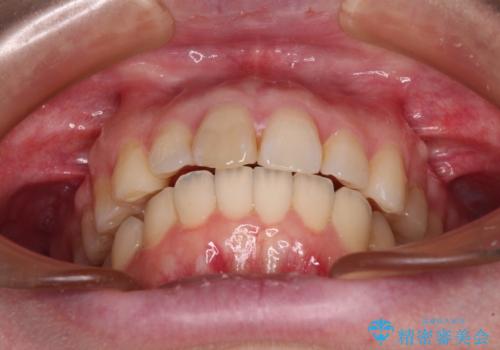

口元の閉じにくさを改善するためには、上顎臼歯を後方に移動させた咬み合わせにする必要があります。

インビザライン単体で改善することも可能ですが、達成する可能性が高くないため、カリエールディスタライザーという補助装置を併用して、より確実性を上げることとしました。

奥歯の咬み合わせを改善しながら、並行してインビザラインで歯列を整えることとしました。